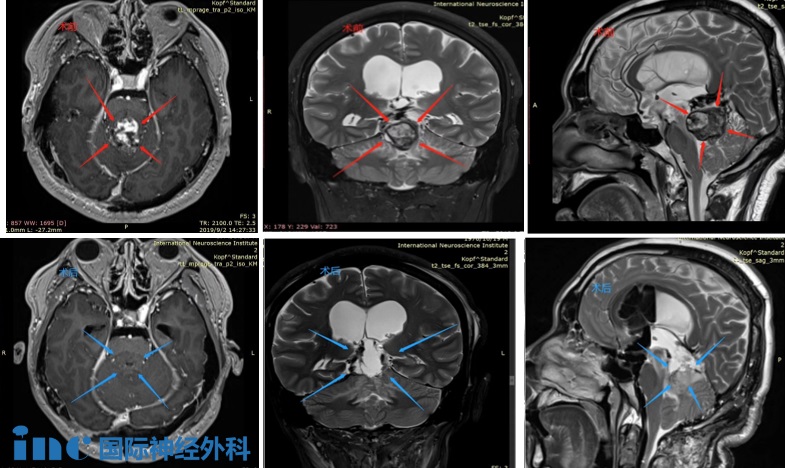

CASE 4:40岁女士-松果体肿瘤

术前(红色):在松果体区域显示出对比度增强的团块,并向下延伸到四脑室。脑干出现水肿。

术后(蓝色):松果体肿瘤被完整切除,无严重神经功能损伤(术后影像为术中磁共振检查时的瘤腔填充物)

病史摘要:40多岁秦女士,头晕、双眼复视,被发现有“松果体及四脑室占位”,4年间辗转治疗,症状仍无缓解,出现肢体无力等。经历了数次伽马刀及立体定向放射外科治疗,症状反而加重,又出现了走路不稳、视力下降、脑积水等其他更多症状。行“松果体区肿瘤切除术”,但只有小部分肿瘤得到切除,术后症状未见明显好转,并逐渐恶化加重。

手术入路:使用小脑幕上、幕下联合入路来到达肿瘤区域实现全切除

术后情况:术后2天即拔除气管,自主呼吸正常,身体体征正常,迁出ICU,复视好转。术后5天在陪同下床康复锻炼,头晕明显好转,肌力好转。术后18天顺利出院,无新发神经功能缺损。